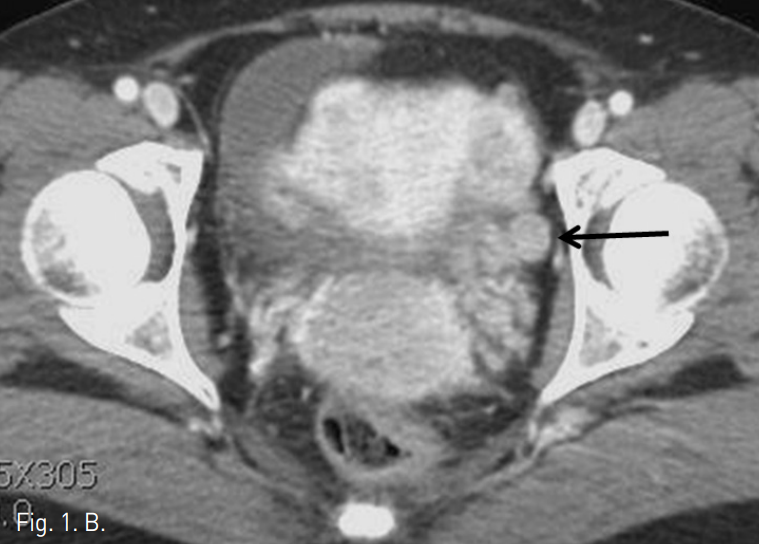

Fig. 1

A, B. Axial CT scan shows 8 x 6 cm sized, convoluted worm-like mass (arrows in A) on the left side of the uterine wall along the uterine vein (arrow in B).